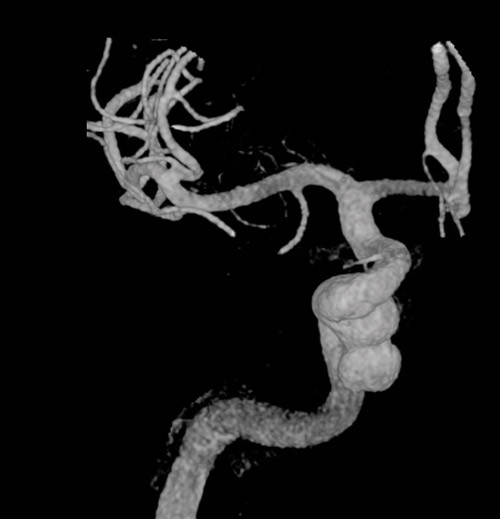

Cerebral CT og CT-angiografi like etter innleggelsen viste ikke tegn til blødning, men man fant på høyre side et intrakavernøst carotisaneurisme med diameter på 10 mm og en beineroderende prosess i sfenoidalsinus og clivus (fig 1, fig 2). MR-undersøkelse av hodet med og uten kontrast bekreftet et aneurisme i mediale del av sinus cavernosus på høyre side og beindestruksjon i samme område (fig 3).

Dagen etter transsfenoidal prøvetaking i narkose fikk pasienten akutt forverring av hodepinen, og det ble tatt en ny cerebral CT og CT-angiografi (fig 4). Den viste at den patologiske prosessen i sfenoidalsinus hadde ekspandert og at aneurismet hadde økt i størrelse til 16 mm i diameter.